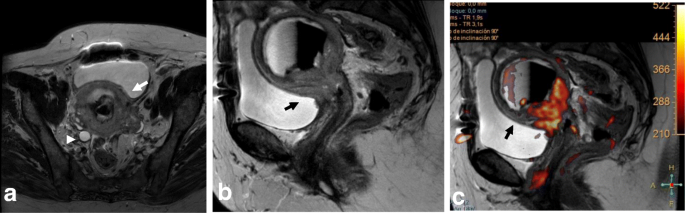

Tumors extending into the mucosa of the bladder or rectum are classified as stage IVA. MRI is an accurate technique for evaluating bladder or rectum involvement, with a sensitivity of 71–100% and specificity of 88–91% [2, 10, 11]. The bladder and rectum are evaluated by cystoscopy and sigmoidoscopy only when the patient is clinically symptomatic. Cystoscopy is also recommended in cases showing a barrel-shaped endocervical growth or where the growth extends to the anterior vaginal wall [26].

Bladder or rectal invasion is suspected in cases showing obliteration of the fatty plane between the cervix and adjacent organs. Tumor presence in the lumen of the bladder or rectum is an unequivocal sign of infiltration and should be confirmed by biopsy and histologic analysis (Fig. 17) [24, 39]. A vesico-cervical fistula is also a sign of advanced disease. DWI and DCE allow better detection of fistula tracts [24, 39, 72]. Bullous edema can lead to false estimation of posterior wall bladder invasion (Fig. 18). DWI and DCE imaging can also help to avoid misinterpreting bullous edema as invasion [2, 11, 70].